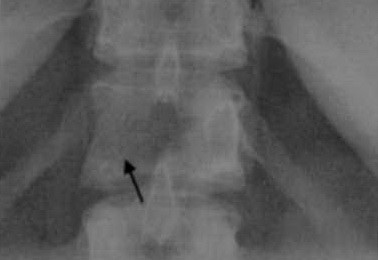

Женщина 34 лет с метастазами карциномы молочной железы. На рентгенограмме позвоночника в прямой проекции определяется деструкция правой ножки дуги Тh 12.